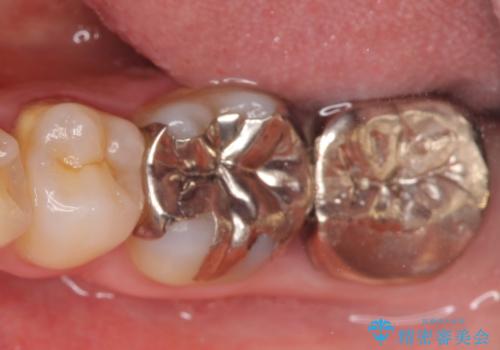

- 左下奥歯で咬むと違和感があるといらっしゃった方の症例です。

検査の結果左下7は失活(歯の神経が死んでいること)しておりX線上で根尖病変を認めたため、根管治療を行いました。

また左下6は遠心にあった歯茎より深い虫歯(縁下カリエス)の問題を解決するため、歯茎を下げる歯周外科手術を行いました。